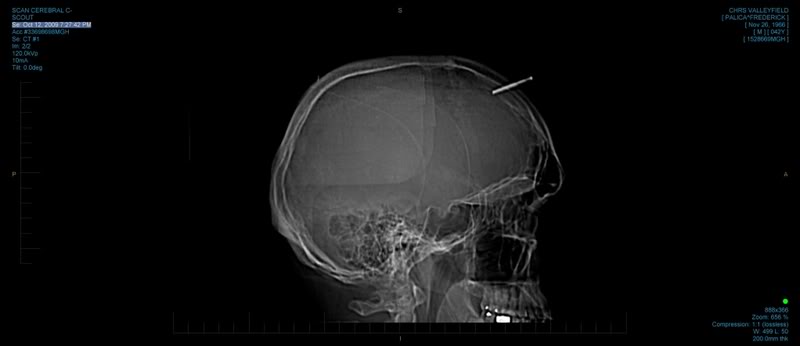

To enter his head at that angle it looks like it must have ricocheted off something first. If that had headed at his eyes I'm not sure safety glasses would have helped with that much force behind it. Holy crap.

The question is, how deep did it go in. Is that a complete file or a chunk of one or something. It might only be a few MM in.

Impressed now? I was impressed with the first pic. Dude's not bleeding and had the presence of mind to snap a pic for all his forum buddies.

You just needed to look at the 2nd page of that thread! Looks like it was a chunk off the end of a 3 sided file.